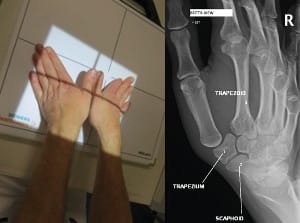

Finally, we must not overlook visualisation all of the peritrapezial joints, better known as the view described by Gedda [9] Kapandji AI, Moatti E, Raab C. La radiographie spécifique de l’articulation trapézo-métacarpienne. Sa technique, son intérêt. Ann Chir Main 1980;34:719-26. and popularised by Taleisnik as Bett’s view [10] Kapandji TG, Kapandji AI. Nouvelles données radiologique sur la trapézo-métacarpienne. Résultats sur 330 dossiers. Ann Chir Main 1993, 12 , N°4, 263-274, which frees up the trapezium perimeter to offer very good visualisation of the whole area (Figure 7). To obtain good quality visualisation of the triscaphoid joint it is useful to take frontal views in ulnar and radial deviation. Some triscaphoid joints appear ‘normal’ on imaging at rest and collapse completely in radial deviation (Figure 8).

Radiological assessment of painful basal thumb arthritis will consist of Kapandji’s frontal and lateral views, an Eaton frontal view (which can replace Kapandji’s frontal view if necessary) and stress view of the TMC, a dynamic triscaphoid view and a Gedda's (Bett’s) view [12], Gedda KO (1954). Studies on Bennett’s fracture: anatomy, roentgenology and therapy. Acta Chirurgica Scandinavica, 193(Suppl): 1. [13] Taleisnik J. The Wrist, 1st edn. New York, Churchill Livingstone, 1985: 95–96. (Figure 9).